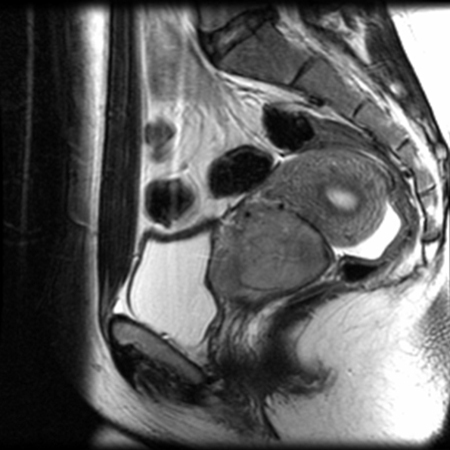

Cáncer de cuello uterino

IRM para la planificación del tratamiento

De la colección de Neil S. Horowitz, MD; utilizado con permiso

Ver esta imagen en el contexto de la/s siguiente/s sección/es: